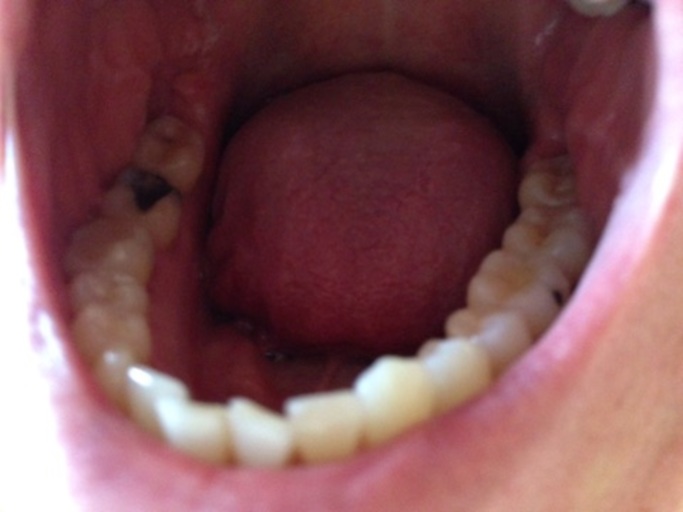

Big hole in tooth

I have a big hole in my tooth that just takes up the middle of my tooth. I don't want to have my tooth out as I have left it for a few weeks and Its going smaller, I want to know if I can have a filling and why is it getting smaller? I don't think there's a nerve it tooth anymore. P.s: there's no pain?

Unless you have had a root canal on the tooth, then the nerve is still there, however it can be necrotic. Once tooth structure is destroyed by the acid producing bacteria in your mouth, it does not grow back. Teeth cannot regenerate. The hole may appear as if it is getting smaller from the trapping of food and plaque which will continue to fill the hole and allow the decay process to continue to progress. It is important for you to not wait until there is pain. Rather, schedule and appointment with your dentist now to restore the tooth. Waiting will put you at risk of pain and will only allow the tooth to get worse and essentially cost you more money to restore.